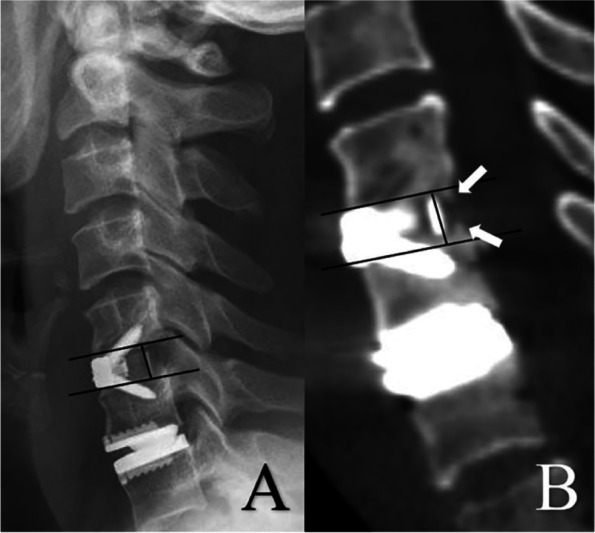

Baseline demographics, clinical and radiological data were collected for all patients. Clinical outcomes were evaluated by the Japanese Orthopedic Association (JOA) scale, Neck disability Index (NDI), and visual analog scale (VAS) for neck and arm pain both preoperatively and at the final follow-up appointment. Pre- and postoperative radiological evaluations included X-ray, CT, and MRI. Lateral and extension-flexion radiographs, sagittal reconstructed CT, and T2-weighted MRI were obtained at specified time points. Segmental ROM at the target level and the ROM of C2-7 was defined as the difference in the Cobb angle between extension and flexion radiographs. For patients with two-level CDR, the mean value of segmental ROM was used for further analysis. Bone mineral density (BMD) was measured at the L2-4 vertebral body. Heterotopic ossification (HO) was using the McAfee classification [19] (Table 1). The classification of bone loss (BL) followed a validated methodology detailed in full elsewhere, based on a classification system reported by Saleh et al. in 2004 [20, 21] (Table 2). For patients with two-level CDR, the more severe degree of HO and BL was recorded. McAfee grade III and IV HO were classified as high-grade HO. Early fusion process was assessed using sagittal reconstructed CT scans at three-month follow-up, measuring the height of new bone tissue at the posterior aspect of the cage (Fig. 1.) For patients with two-level ACDF, the mean value of new bone tissue was used for further analysis. The criteria to confirm fusion at 1-year were segmental ROM less than 3° in X-ray and continuous bone bridge demonstrated in CT imaging. For patients with two-level ACDF, if both levels had achieved fusion they were classified as “fusion”, otherwise they were classified as “non-fusion”. All measurements and ratings were completed by two independent spine surgeons, with corroboration by a third senior spine surgeon in case of disagreement.

Fig. 1.

A lateral X-ray at 3-month follow-up was used to confirm the shape of endplates and the location of the marker line (A). The height of bone tissue along the posterior border of the cage was measured in the sagittal CT scan as the reflection of early fusion effect. (The white arrows in B)